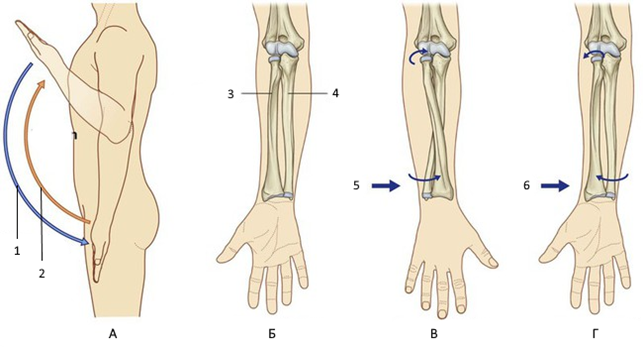

РОЗПІЗНАЙТЕ ДИСТАЛЬНИЙ ПРОМЕНЕВО-ЛІКТЬОВИЙ СУГЛОБ.

ПЕРЕЛОМ ЯКОЇ КІСТКИ І ЯКОЇ ЇЇ ЧАСТИНИ ВИ БАЧИТЕ НА РИСУНКУ?

РОЗПІЗНАЙТЕ КІСТКУ. ПЕРЕЛОМ ЯКОЇ ЇЇ ЧАСТИНИ ВИ БАЧИТЕ НА РЕНТГЕНОГРАМІ?

СКЛАДНИЙ СУГЛОБ (ЯК ВИЛКА). Є ВСІ ПЕРЕДУМОВИ ДЛЯ РОЗТЯГНЕННЯ ЗВ'ЯЗОК І ЗМІЩЕННЯ КІСТОК. РОЗПІЗНАЙТЕ СУГЛОБ.